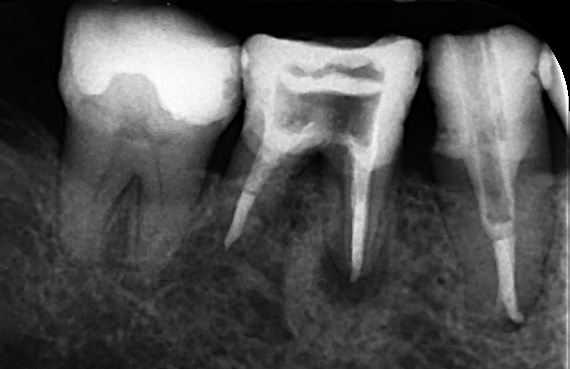

下の画像は、根管治療されていた大臼歯の初診時のCT画像です。根の先には根尖病変の炎症像は特にみられませんでした。他の歯の治療後の経過観察中に膿ができてきたケースです。根管治療が必要になったので、通法通り再根管治療を行い、膿は改善しました。